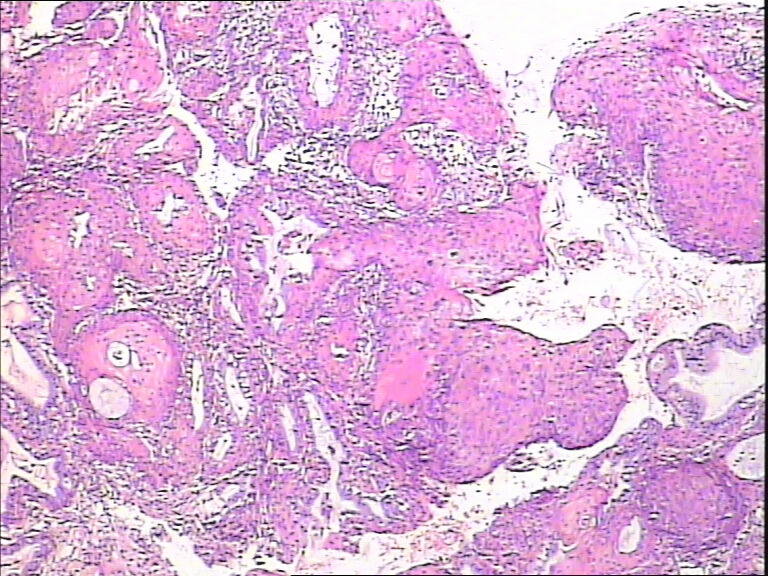

45y,触血,宫颈多点活检。

• 求教!宫颈图1

图1